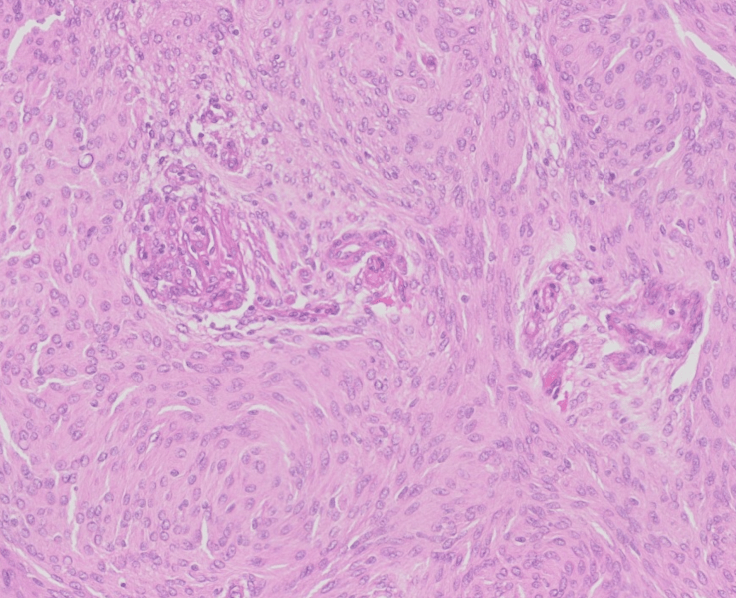

Meningiomas, like the one pictured here, typically show whorling architectural pattern and nuclear pseduoinclusions. The vast majority of meningiomas are low grade (WHO Grade 1) dura-based tumors with good prognosis following complete resection. However, recent studies have suggested that endothelial cell hypertrophy and/or microvascular proliferation in an otherwise typical meningioma are correlated with shorter progression free survival.